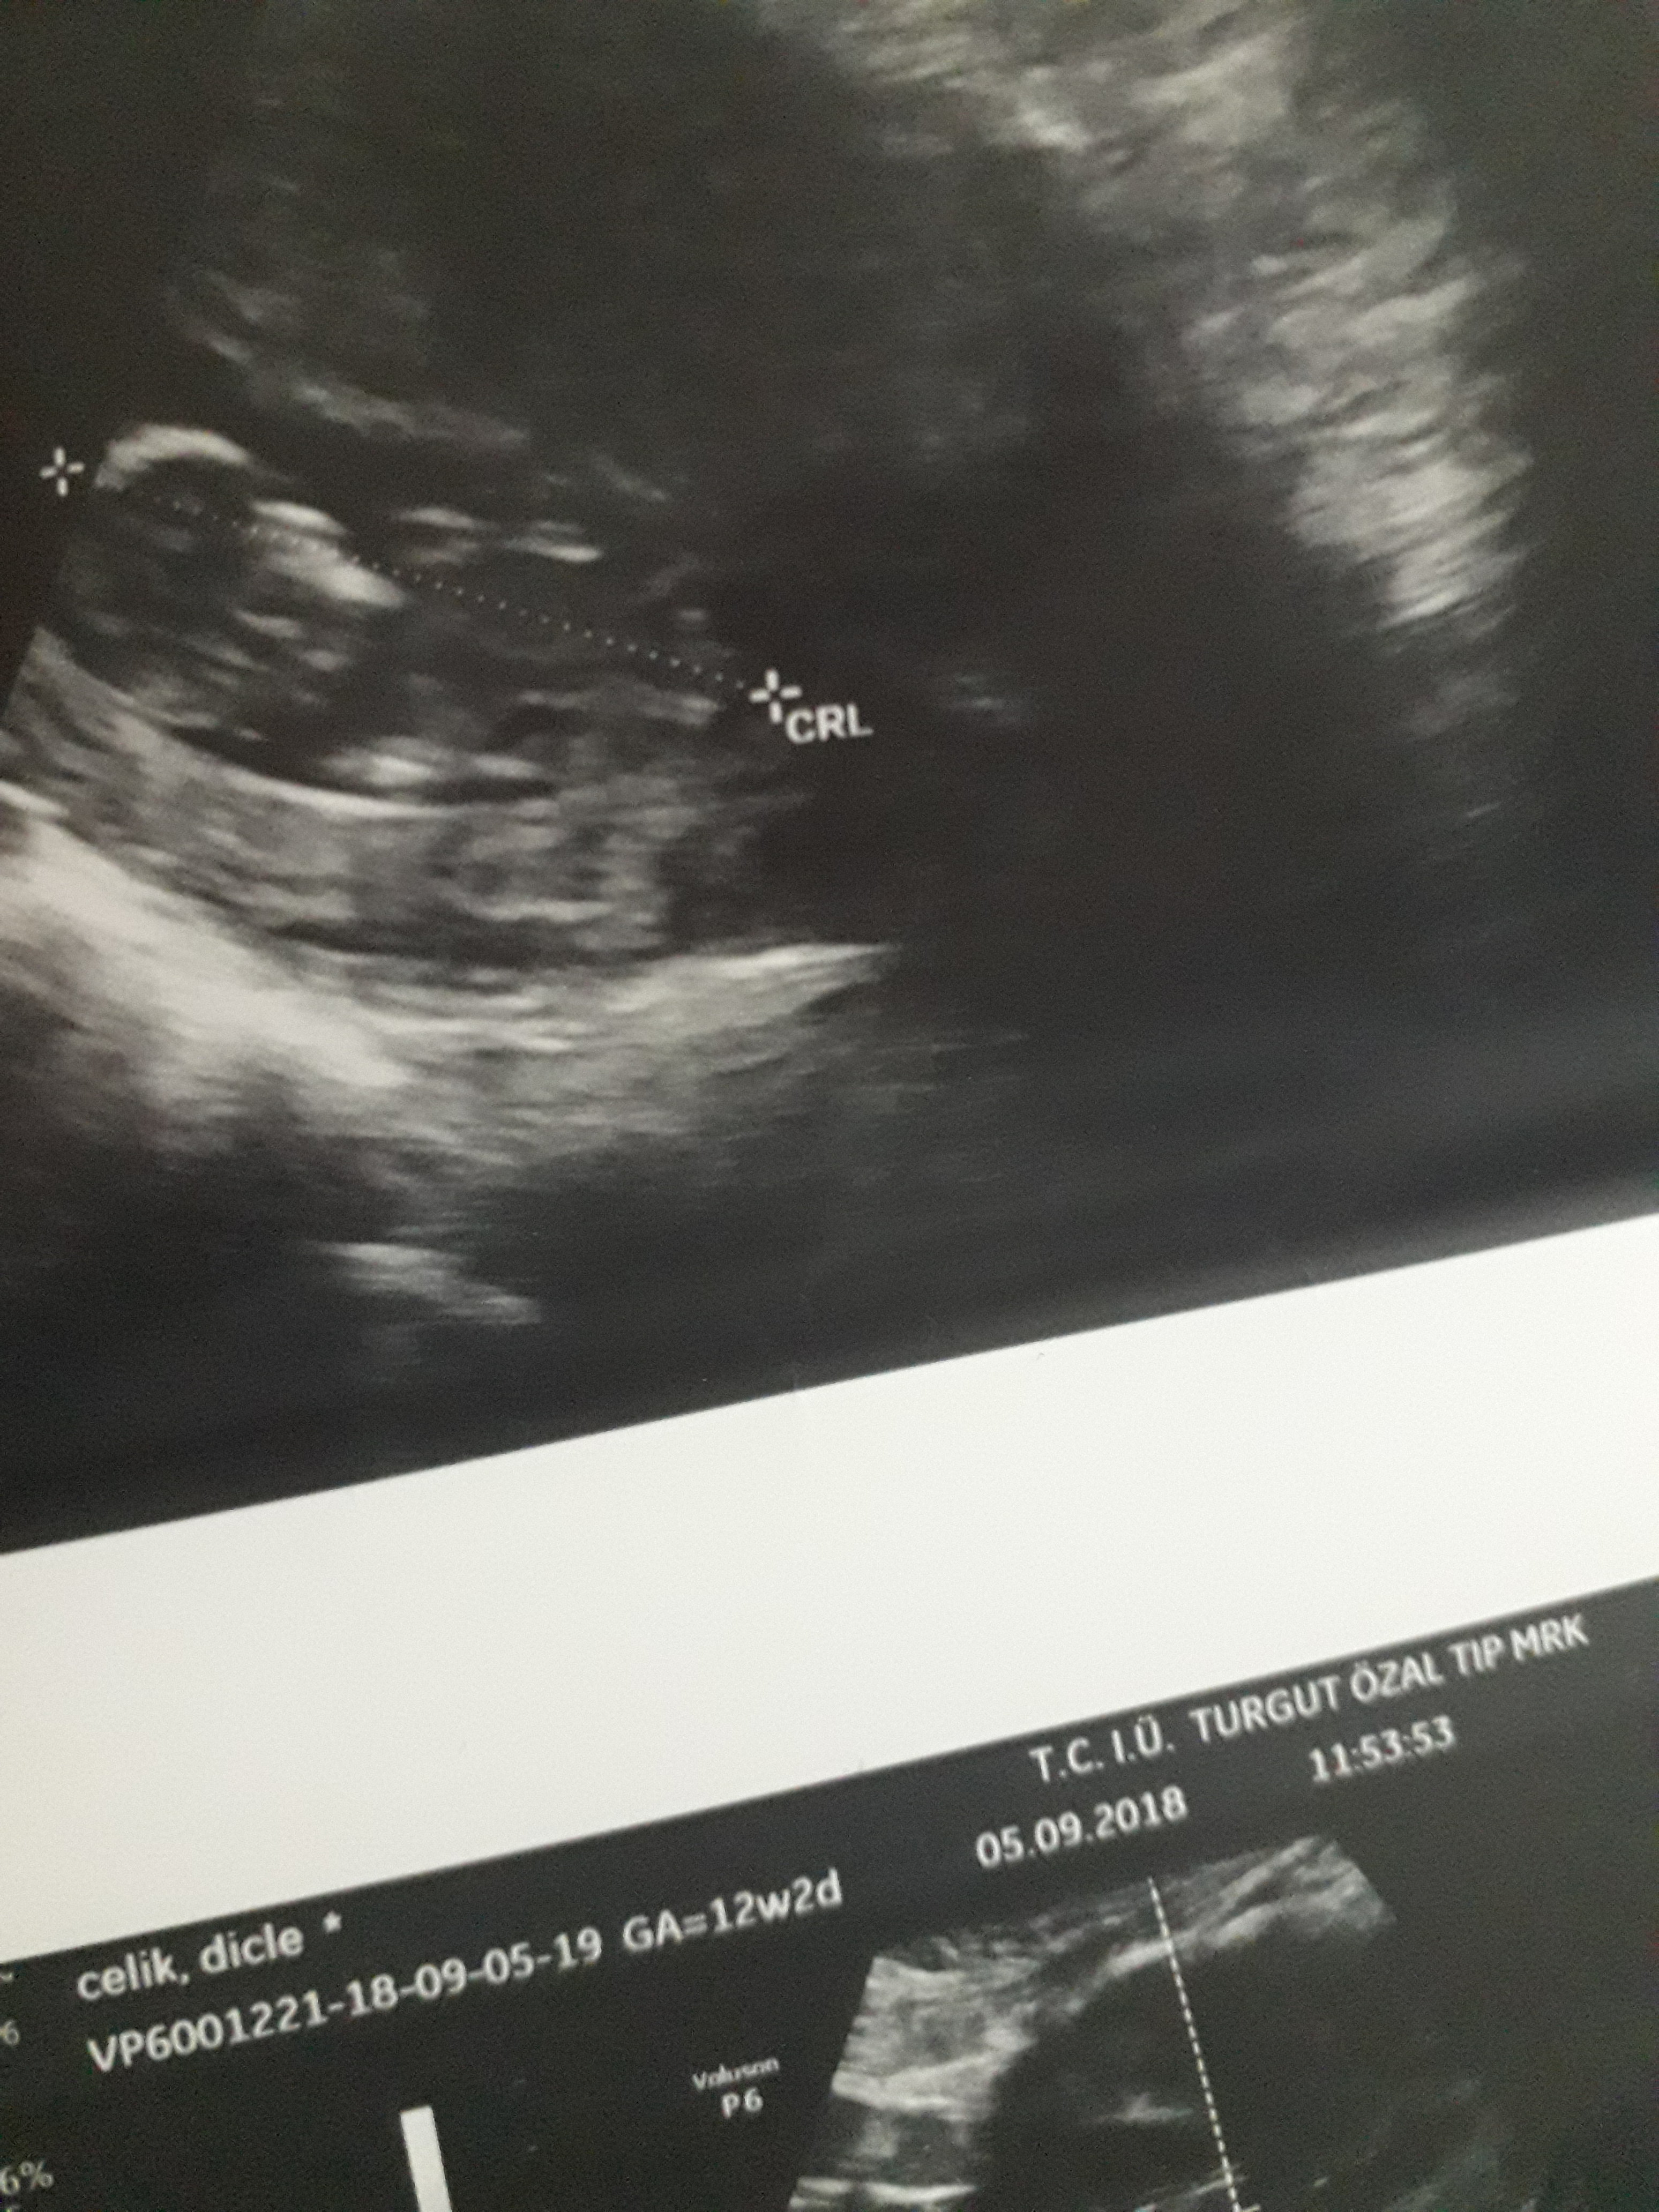

Dun malatyada verildi 12 +4 gunluk lutfen yorumlayin

Dun verildi 12 haftalik lutfen yorumlayin

Görsellerde nub çıkıntısı belli değil . Ultrasonu yapan doktor cinsiyeti hakkında bilgi vermiştir mutlaka ama şunu belirtmeden geçmeyeyim. Bu haftalarda cinsiyet tahmininde yanılma payı çok yüksek 17-19 ve 20 ci haftalarda bebeğin cinsiyetini net olarak öğrenebilirsiniz.